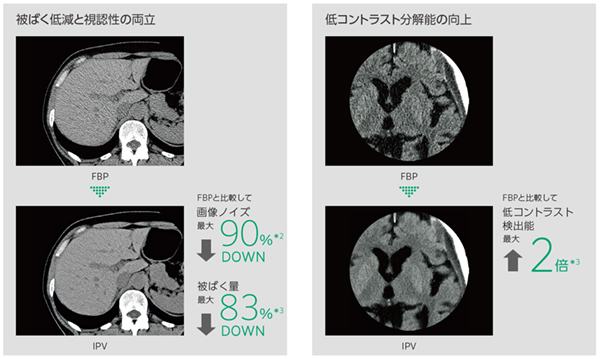

富士フイルムの経験とAI技術の活用*4により,被ばく低減と視認性を両立

IPV*5はAI技術を活用して開発した画像再構成技術です。充分な反復処理により得られる画像を教師データとして,高精度の処理を高速化しました。

IPV:AI技術を活用して設計された逐次近似処理